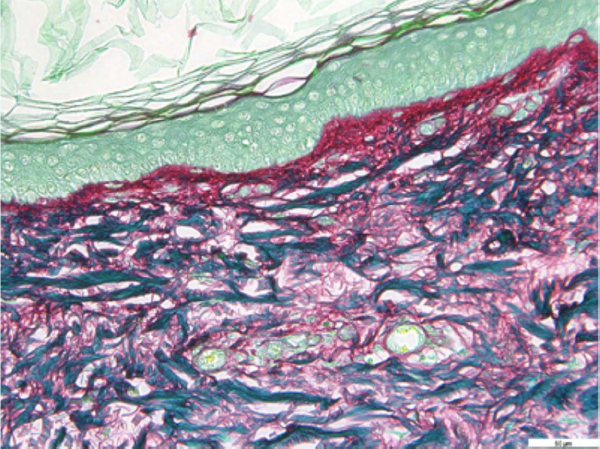

Da ogni biopsia sono state ricavate due sezioni di pelle, per un totale di dodici, e sono state poi colorate utilizzando la colorazione istomica Picrosirius Red che evidenzia con una tonalità rosso porpora le fibre di collagene.

Per la valutazione del collagene è stato selezionato il derma papillare, poiché è la regione dermica più suscettibile alle modifiche del collagene in risposta ai trattamenti. Per l’analisi di immagine è stato utilizzato un software AI sviluppato su misura, creato da Phyton, che identifica automaticamente la lamina basale che separa l’epidermide dal derma. Il software valuta l’intensità della colorazione rossa, generando un punteggio direttamente correlato al contenuto di collagene nel derma papillare. Sono state acquisite e analizzate 12 immagini per ciascun trattamento.

Campione di pelle non trattato con Liftable Exoserum, dopo aver applicato la colorazione che evidenzia le fibre di collagene

Campione di pelle dopo 5 giorni di trattatamento con Liftable Exoserum, dopo aver applicato la colorazione che evidenzia le fibre di collagene (+26%)